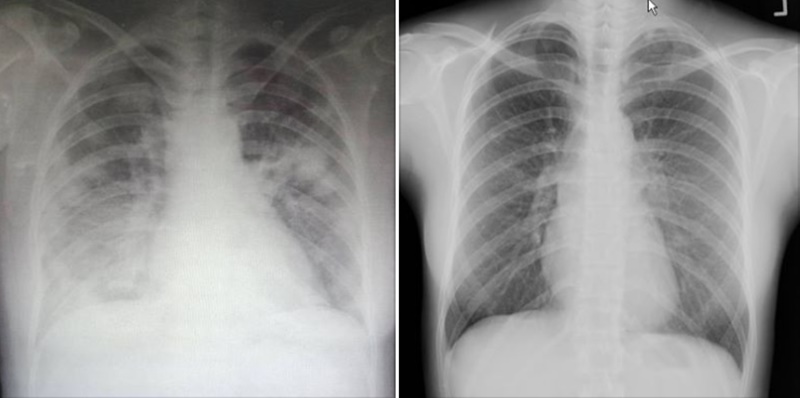

ทั้งนี้ ภาพทางซ้ายมือ จะเป็นภาพของผู้ป่วยโควิด 19 ส่วนภาพทางขวามือ จะเป็นภาพของปอดคนปกติ โดยเมื่อเทียบกันแล้ว ภาพคนปกติจะไม่มีฝ้าขาวในปอดแต่อย่างใด ต่างกับคนที่ป่วยโควิด 19 ฝ้าขาวจะเห็นเด่นชัดในฟิล์มเอกซเรย์